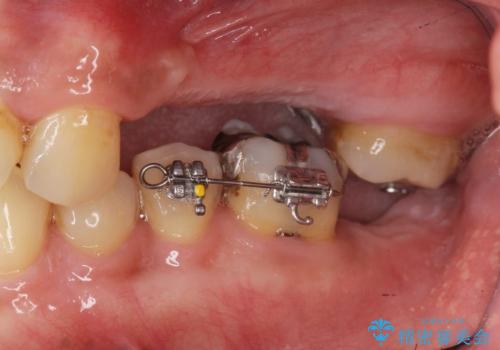

・対合歯の欠損による歯の挺出→マイクロインプラントを用いた小矯正を行うことで咬合平面を是正

今回、左下6は頬側歯頚部に虫歯があり圧下を行ったことからクラウンにより補綴を行いました。